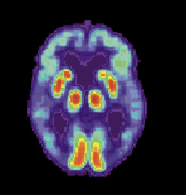

当前,美国标准的诊断阿尔茨海默症的方法,总体上属于排除法,因为痴呆可能是多种原因引起的,又没有高精度的针对性测试工具,只能把其它原因都排除后,再定性为“可能的阿尔茨海默氏痴呆”,实际意思是找不到其他导致痴呆的原因。在这一过程中,医生会反复询问患者的整体健康信息,使用哪些处方药和非处方药、饮食、病史、日常活动能力以及行为和性格变化等,还要反复做记忆力、问题解决、注意力、计数和语言等方面的测试,然后是标准医学检查,例如血液和尿液检查,以确定诱发痴呆问题的其他可能原因,最后执行脑部扫描,例如CT扫描,核磁共振(MRI)或PET扫描,以彻底排除其他可能的原因。当然,患者去世后,将临床措施与尸检中的脑组织检查相结合,可以肯定地诊断出阿尔茨海默氏病。了解医生面对的这一诊断困难局面,便可以理解为什么血液检测技术会引发业内轰动了,这不仅是在解决医学问题,也是在解决社会问题。虽然目前还没有治疗阿尔茨海姆症的特效药,任何一种药物或其他干预措施都不可能成功治愈它,但是,即使无法停止或逆转潜在的疾病过程,也可以通过对疾病过程早期介入,将患者的日常功能维持一段时间,并减缓某些问题,如记忆力减退。早期诊断还有一个重要作用是,它可以帮助家庭计划未来,患者因而有时间处理财务和法律事务,家人有时间解决患者潜在的安全问题,了解患者生活安排,社区也可以由此建立相应的支持网络。 图注/这张脑部PET图像,显示这名患者的颞叶功能丧失。是老年痴呆的典型症状。